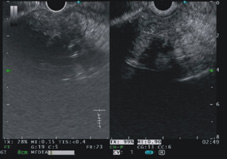

圖二、顯示傳統的內視鏡超音波偵測病灶血流的能力不儘理想

圖三、顯示對比增強諧波內視鏡超音波(Contrast-enhanced harmonic EUS)可以凸顯病灶血流豐富的程度(畫面右邊變的較亮)